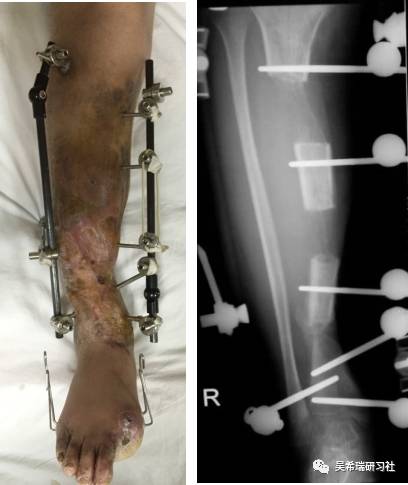

小腿骨折继发感染骨髓炎反复皮瓣9个月未下地骨质疏松继发肥胖

TIPS:9个月反复皮瓣未下地骨质严重疏松病灶清除后应用表面羟基磷灰石涂层骨圆钉半开放植骨 + 骨搬移骨水泥设计为自行吐出伤口开放换药走路骨质改善、骨愈合治疗足下垂